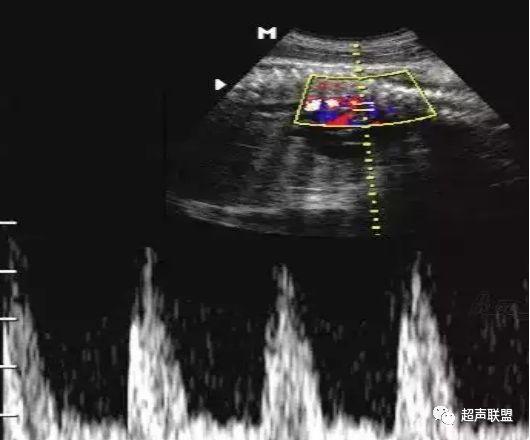

4 脐静脉频谱

胎儿宫内缺氧严重时脐静脉出现搏动。

6、脐静脉:脐静脉搏动(见于严重的胎儿宫内缺氧);

图9 脐静脉搏动